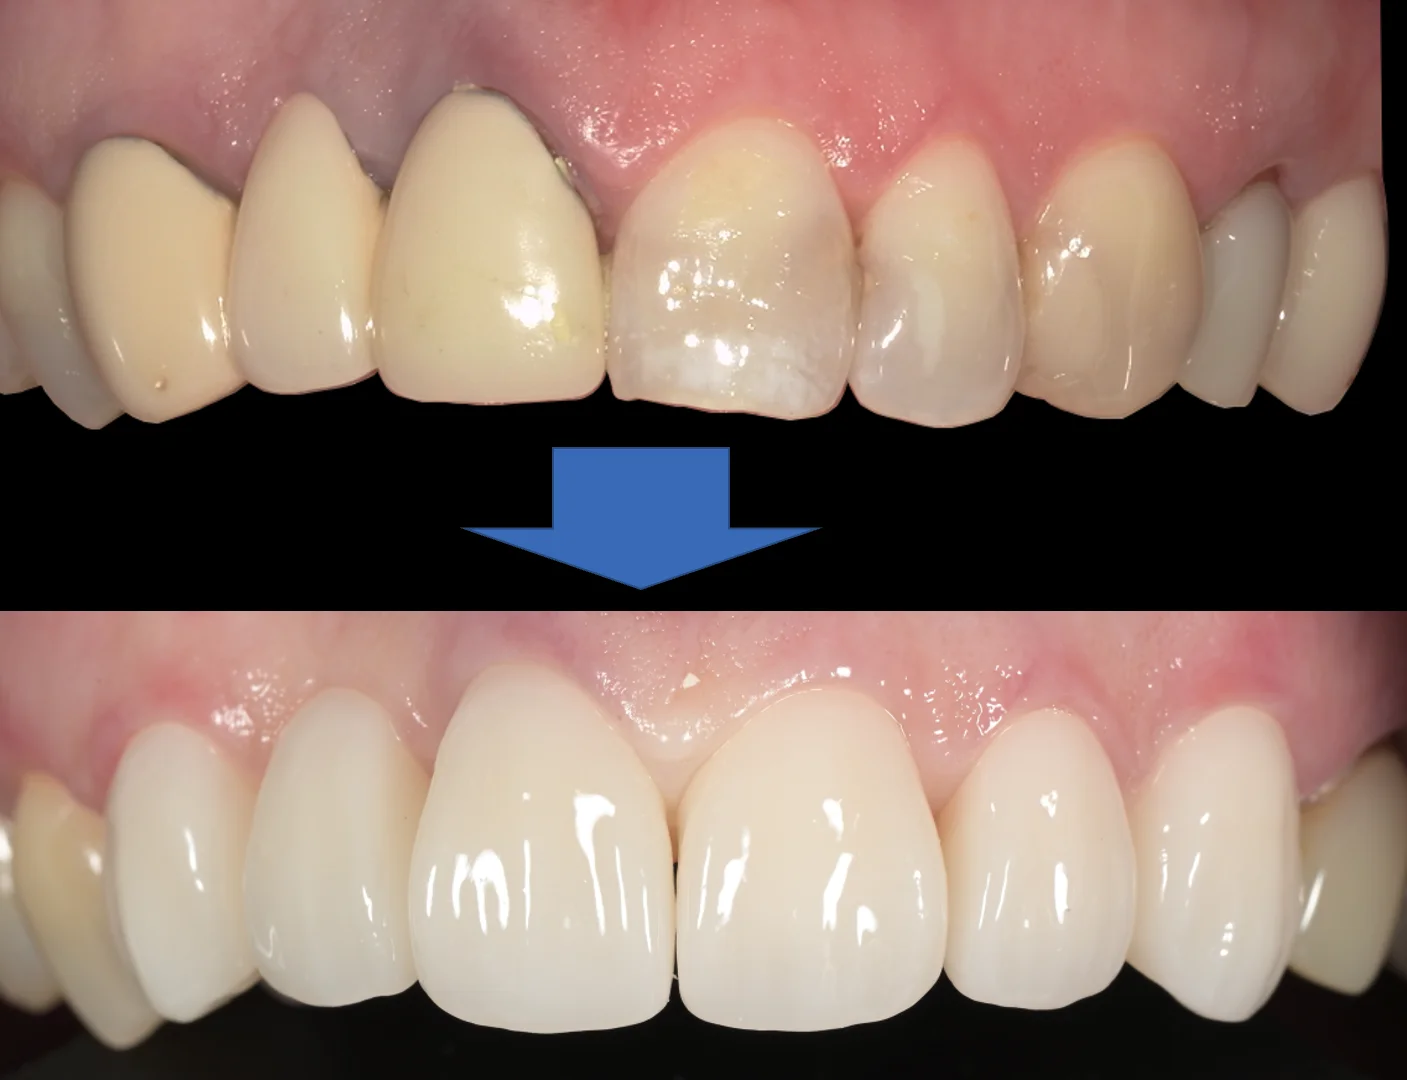

術前術後です。

撮影日が別日のため、画角がずれてしまっていますが、随分と見た目が綺麗になったのはわかると思います。

長期間・複数回にわたる治療、お疲れ様でした!

歯茎に関してはこの後のブラッシングでさらにあってくると思われますので、引き続きこの調子で定期管理に来つつ、セルフケアも頑張っていただければ相当持つと思います。